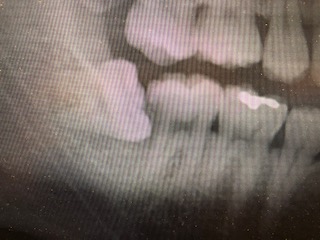

・親知らずに症状はないが、手前の歯に虫歯ができてしまった場合

歯と歯の間に食べかすが詰まりやすく出てこないため、親知らずの手前の歯に虫歯を作りやすいのです。

そうなった場合は邪魔になっている親知らずを抜いてから、手前の歯を治療していきます。

本人の自覚がないままかなり深くまで虫歯が進行するケースがあるので注意が必要です。